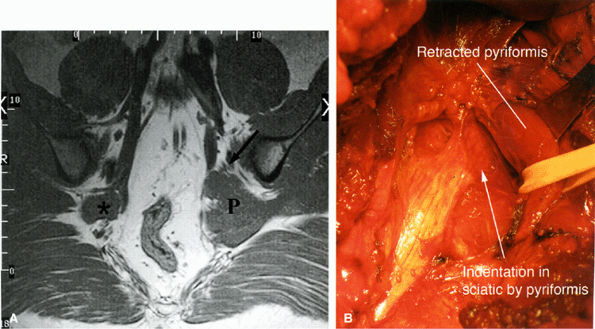

FIGURE 6.16 ● Surgically proven left piriformis muscle syndrome. (A) Axial T1-weighted image demonstrates a markedly enlarged left piriformis muscle (P) displacing the sciatic nerve (arrow). The normal right piriformis (asterisk) is much smaller. (B) A posterior view during surgery demonstrates indentation on the left sciatic nerve from the piriformis muscle. (Courtesy of Stephen Russel, MD, NY)

|

Significant asymmetry in the piriformis muscles is noted between the symptomatic and asymptomatic sides (Figs. 6.16 and 6.17). Mild asymmetry of the muscles, however, is often present in asymptomatic individuals.

Presence of selective atrophy49,50 or hypertrophy of the piriformis muscle and accessory muscle slips47,52

Detection of the sciatic nerve or one of its divisions within the substance of the piriformis muscle. An intramuscular location of the sciatic nerve, however, may be a normal variation in up to 10% of individuals.

Increased signal in the nerve and in the piriformis muscle may also be seen.49